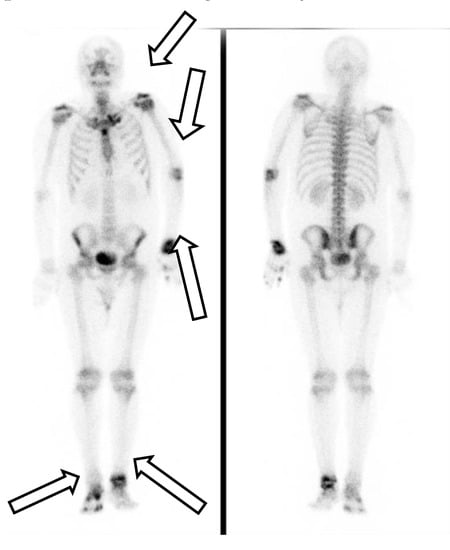

His first admission was to the division of infectious diseases. The 2019 novel coronavirus disease (COVID-19) had been excluded after repeated blood sampling and plain X-ray films of the chest. Blood tests showed a white blood cell count of 12,850 cells/mm3, hemoglobin level of 13.3 g/dL, platelet count of 490,000 cells/mm3, plasma creatinine level of 1.0 mg/dL, alanine aminotransferase (ALT) level of 79 U/L, aspartate aminotransferase (AST) level of 38 U/L, and c-reactive protein (CRP) level of 15.00 mg/L. Serum tests did not identify viral hepatitis infection. Microbiology examination of the sputum, blood, urine, and feces did not identify any pathogens. Blood sampling did not detect any autoantibodies. Physical examination did not reveal abnormal murmurs of the heart or abnormal primitive neurologic reflexes. Plain X-ray films of the chest did not show mass lesions or abnormalities in the lungs. X-ray of the major joints of all limbs did not show fracture, erosion of bones, or abnormalities of soft tissue. A technetium-99m methylene diphosphonate bone scan revealed increased uptake in the left shoulder, elbow, wrist, and ankle, and right foot and toes, which was compatible with the clinically significant arthritis noted in the physical examination (Figure 1). The patient’s fever did not respond to antibiotics for 2 weeks from the first admission. Reactive arthritis was suspected initially because no significant pathogens or autoantibodies had been identified, and sterile inflammation was suspected. The fever responded to daily systemic methylprednisolone (40 mg), and the patient was discharged 17 days after the first admission.

Figure 1. A technetium-99m methylene diphosphonate bone scan revealed increased uptake in the left shoulder, elbow, wrist, and ankle, and right foot and toes.